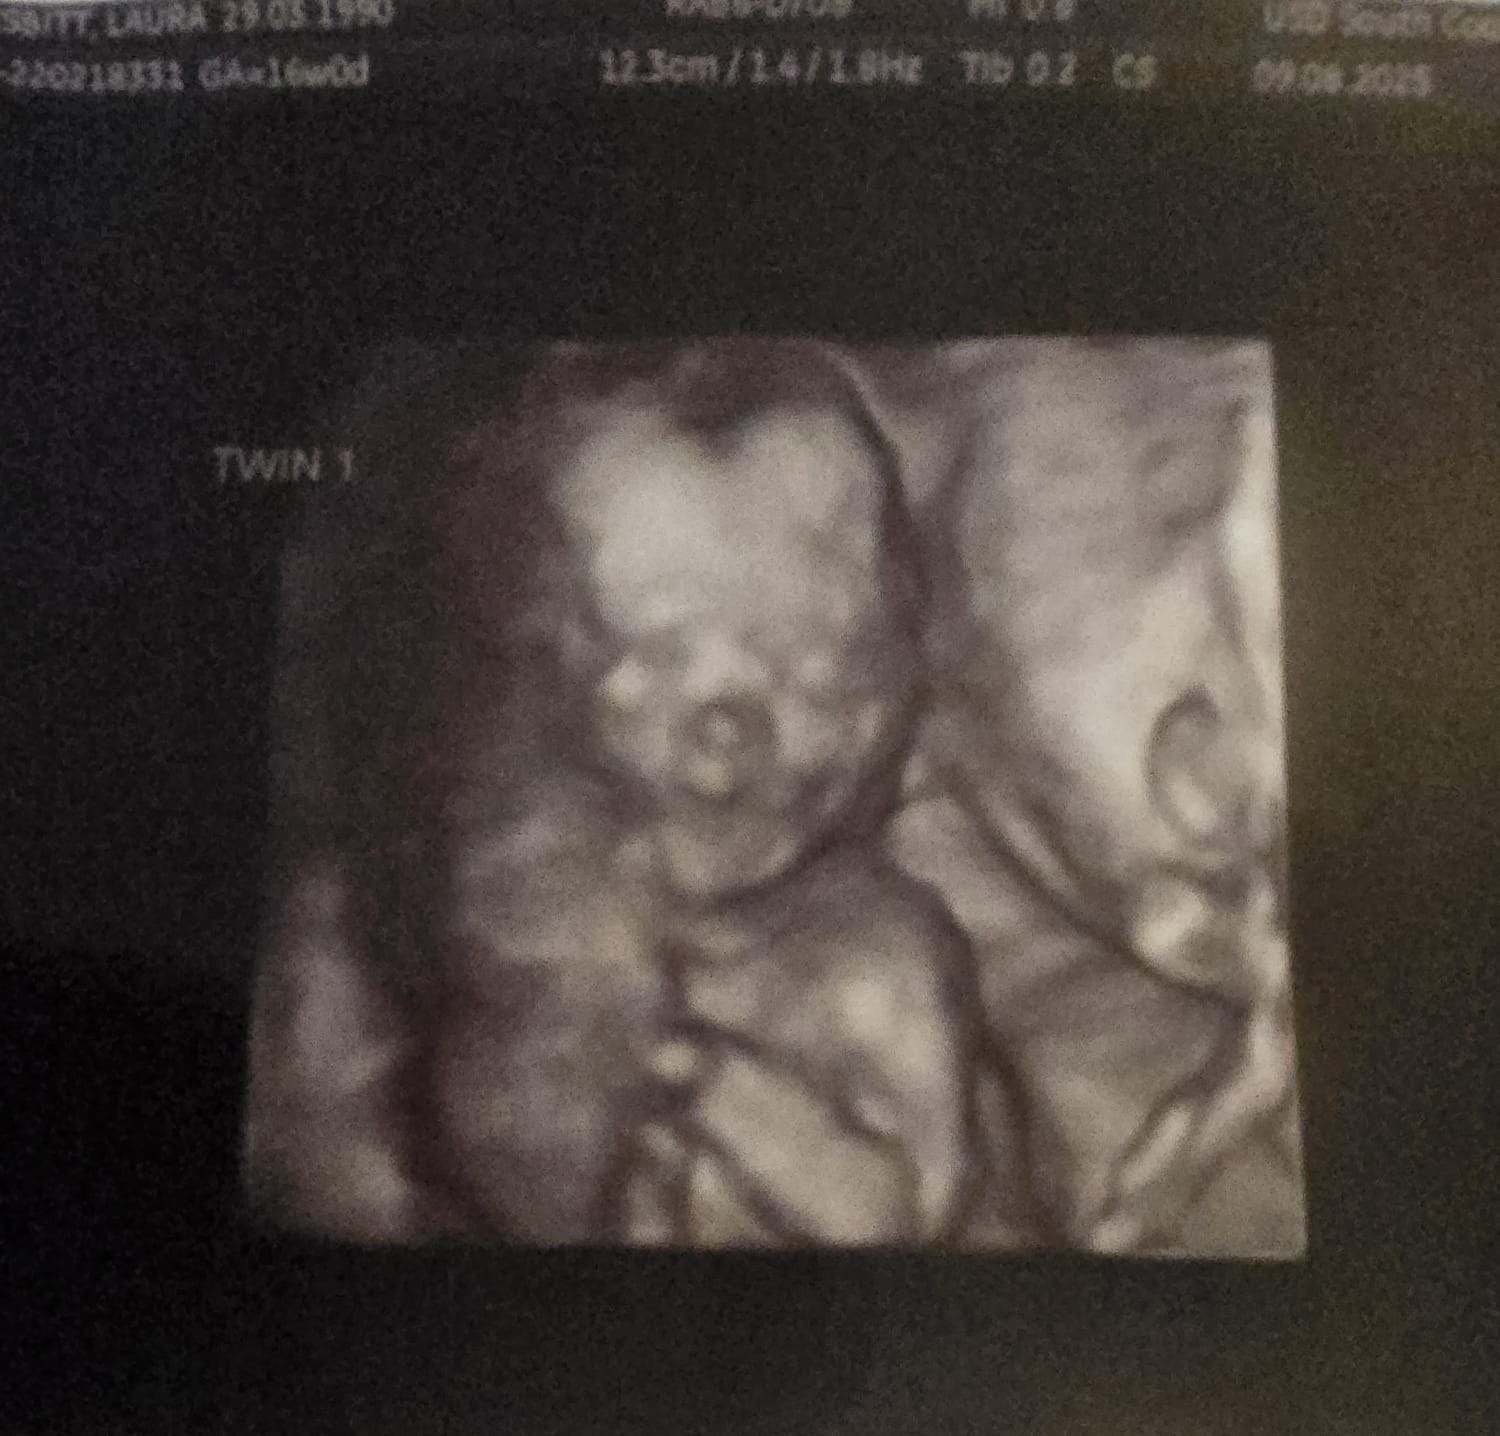

So we went to our 12week scan to surprisingly find out we are having identical twins. This was a big shock! But very happy to find this out. We then went to our 16weeek scan to find out that 1 baby is behind by 1 week compared to the other this is called TTTS with twin 1 being smaller and not getting enough fluid then twin 2 this is called - TWIN TO TWIN TRANSFUSION SYNDROME. We now have been refered to St George's twin specialist hospital in London to monitor and to have laser treatment to make sure they give both twins a good fighting start and to give the other twin that's developing behind more blood flow and nutrients.